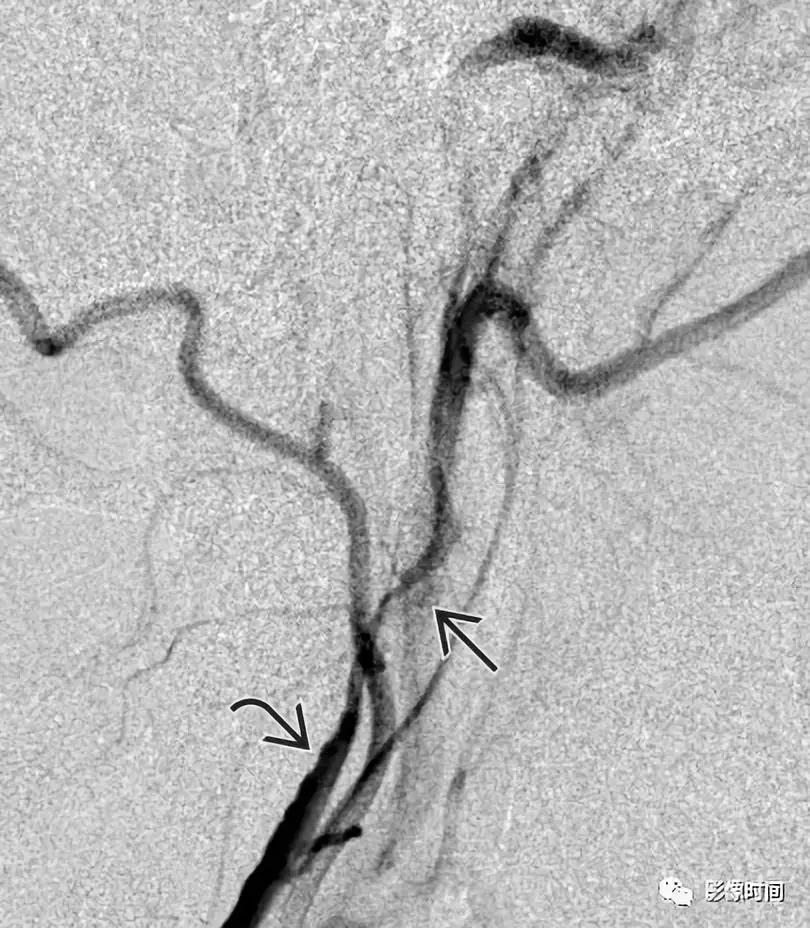

模式图显示迷走神经球瘤位于约颈 1 水平,富含血管,颈内动脉受压向前内移位。T2WI 显示一个边界清晰高信号肿块 (白色箭头) 与流空血管 (黑色箭头)。注意右颈内动脉 (i) 和颈外动脉 (e) 的前移位,右颈内静脉外移位(j)。DSA 显示颈动脉分叉处上方高血管团块 (白箭头)。